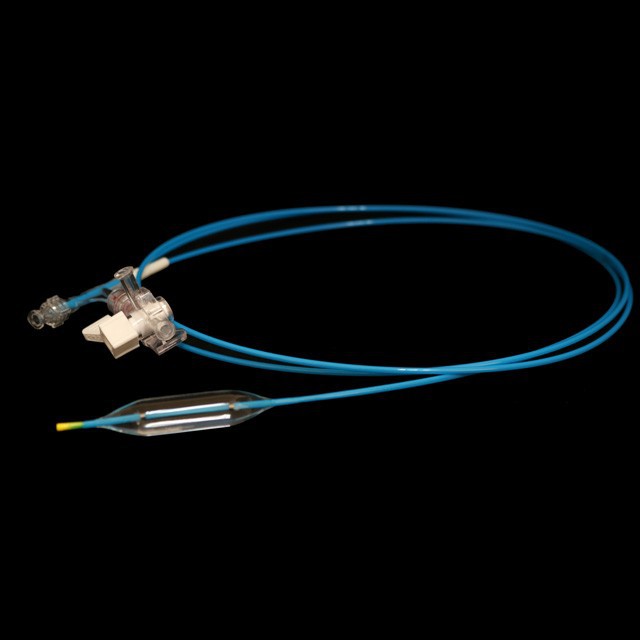

● idoneam adultis et adolescentes in DIATRUM operationem digestivorum tractu stricture sub endoscopes .

● elastica mollis consilium consilium, quod potest aequaliter intrare in scopum positus cum minus damnum .

● celeri INCILE Design adjuvat ad redigendum surgery tempus .

● optimal consilio fistulam facit eam lenis et boni elasticitate, fortis torquens resistentia et facilius passability .

● Pre-input 0 {{II}} XXXV "Guide filum cum mollis tip et marcam, quae est facillimus estimate longitudinem in medio Guide filum.